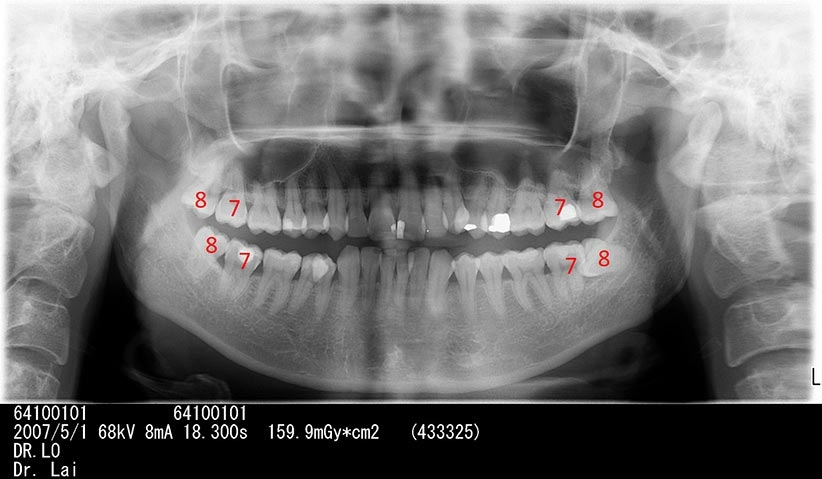

不拔智齒後果

左右下牙兩顆智齒不聽醫師建議拔除,5年後,智齒前面大牙也因智齒而蛀牙,最後拔除4顆牙

左下智齒不聽醫師建議拔除,5年後,智齒前面大牙也因智齒而蛀牙,最後拔除2顆大牙